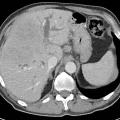

Allerdings hat diese Form der kontinuierlichen Druckatmung, die im Eurofighter in Abhängigkeit von der Gz-Belastung bis zu 60mmHg erreichen kann, auch einige unerwünschte Nebenwirkungen, die in vergangenen Vergleichsuntersuchungen verschiedener Anti-G-Anzüge als flugsicherheitsrelevant eingestuft wurden. Hier sind vor allem ein mit ihr einhergehender, zum Teil heftiger Armpain, die Beeinträchtigung der Sprachverständigung, Ohr- und Sinusblöcke, sowie Nebenwirkungen auf das Atmungssystem zu nennen. Der relativ hohe Druck und die trockene Luft führen zu mechanischen Irritationen in den zuführenden Atemwegen. Die Ausatmung ist erschwert und der normale Aktivitätszyklus der Atmung mit aktiver Inspiration, d. h. Einatmung durch Unterdruck und passiver Exspiration, wird umgekehrt. Durch die Dislokation von Lungengewebe infolge der Gz-Beschleunigung und den hohen Druck kommt es zur Dehnung und Weitung der apikalen Alveolen mit der Gefahr für einen Spontanpneumothorax und die Ausbildung eines subpleuralen Emphysems.

Obwohl valide Studien zu gesundheitlichen Auswirkungen der PPG insbesondere auf das Atmungssystem im fliegerischen Kontext bisher fehlen, weiß man aus klinischen Settings, das eine positive Druckbeatmung mit weitaus geringeren Drücken als sie in der Luftfahrt gebräuchlich sind, bereits zu einer Lungenschädigung führt. Daher wäre ein Anti-G-Anzug, der auf eine solche Atmungsform verzichtet und dennoch einen verlässlichen Anti-G-Schutz bietet, zweifellos erstrebenswert.